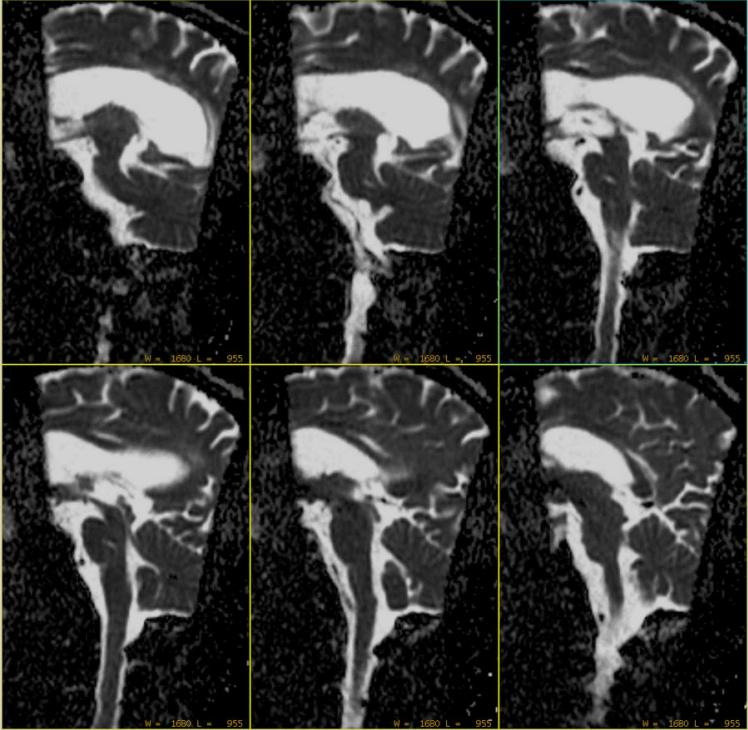

回顾本病例,AX DWI定位线如下: